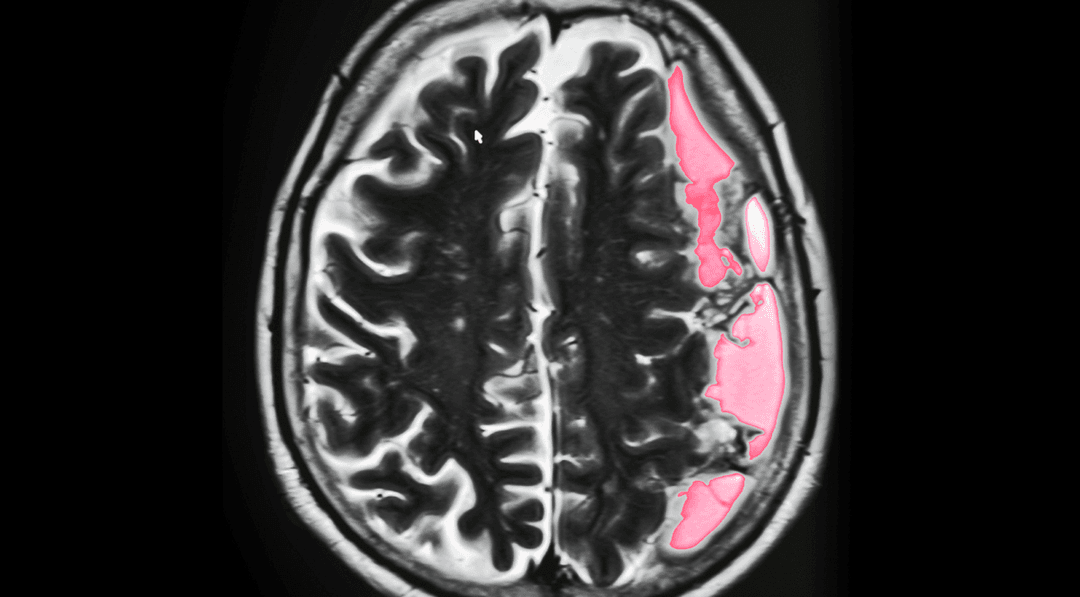

النزف تحت العنكبوتية: الأسباب والأعراض والتشخيص والعلاج

9 ديسمبر ، 2019

النزف تحت الجافية: الأسباب والأعراض والتشخيص والعلاج